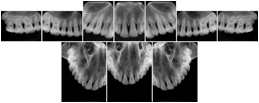

OO.1.2 Ophthalmology

1. A patient in rural Canada visits a general ophthalmologist and is found to have diabetic macular edema. The general ophthalmologist would like to discuss the case with a retina specialist before performing laser surgery. A fluorescein angiogram is done with multiple retinal images taken in a timed series after an intravenous injection. The images along with a Structured Display are shared via a Health Information Exchange with a retina specialist in Calgary, who opens them using his Ophthalmology EMR software and consults via phone with the general ophthalmologist. Both physicians view the images in the same layout so the retina specialist can provide accurate guidance for treating the patient.

2. A patient in rural Iowa visits his primary care physician for management of diabetes. Three non-mydriatic (patient's eyes are not dilated) photographs are taken of the back of each eye, and forwarded electronically along with a Structured Display to an ophthalmologist in Iowa City. The ophthalmologist reads the photos in an agreed upon layout so there is no mistake about what portion of which eye is being viewed. The ophthalmologist is able to tell the primary care physician that his patient does not need to come to Iowa City for face to face ophthalmologic care, but that there is a particular view of the left eye that should be photographed again in 6 months.

Ophthalmic Retinal Study Structured Display

Figure OO-3. Ophthalmic Retinal Study Structured Display

3. A patient in rural Minnesota experiences sudden vision loss and goes to a general ophthalmologist, who acquires OCT images and forwards them electronically along with a Structured Display to a retina specialist six travel hours away. The retina specialist is able to view the images in the standard layout that he is comfortable with, and to confirm that the patient has a choroidal neovascular membrane. He determines that is would be worthwhile for the patient to travel for treatment.

OCT Retinal Study with Cross Section and Navigation Structured Display

Figure OO-4. OCT Retinal Study with Cross Section and Navigation Structured Display